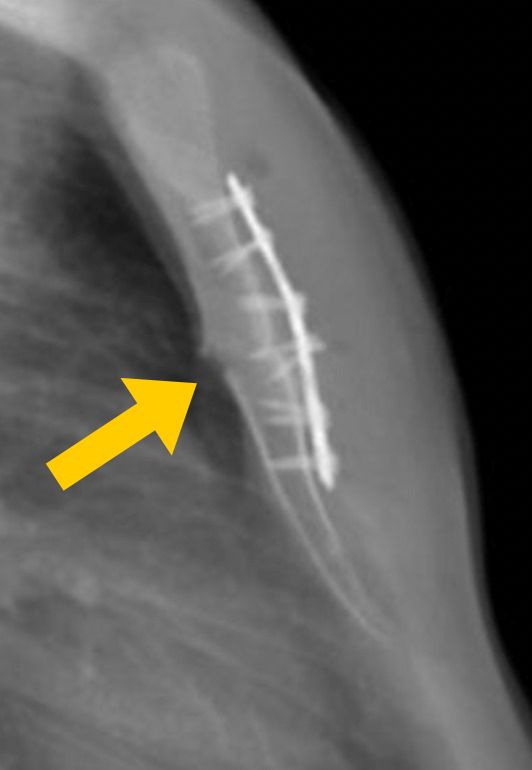

Ameliyat sırasında, sternum (iman tahtası) ile kaburgalar arasındaki düzensiz kıkırdak segmentleri çıkarılır,

ardından sternum doğru anatomik konumuna getirilir ve gerekirse destekleyici materyallerle stabilize edilir.